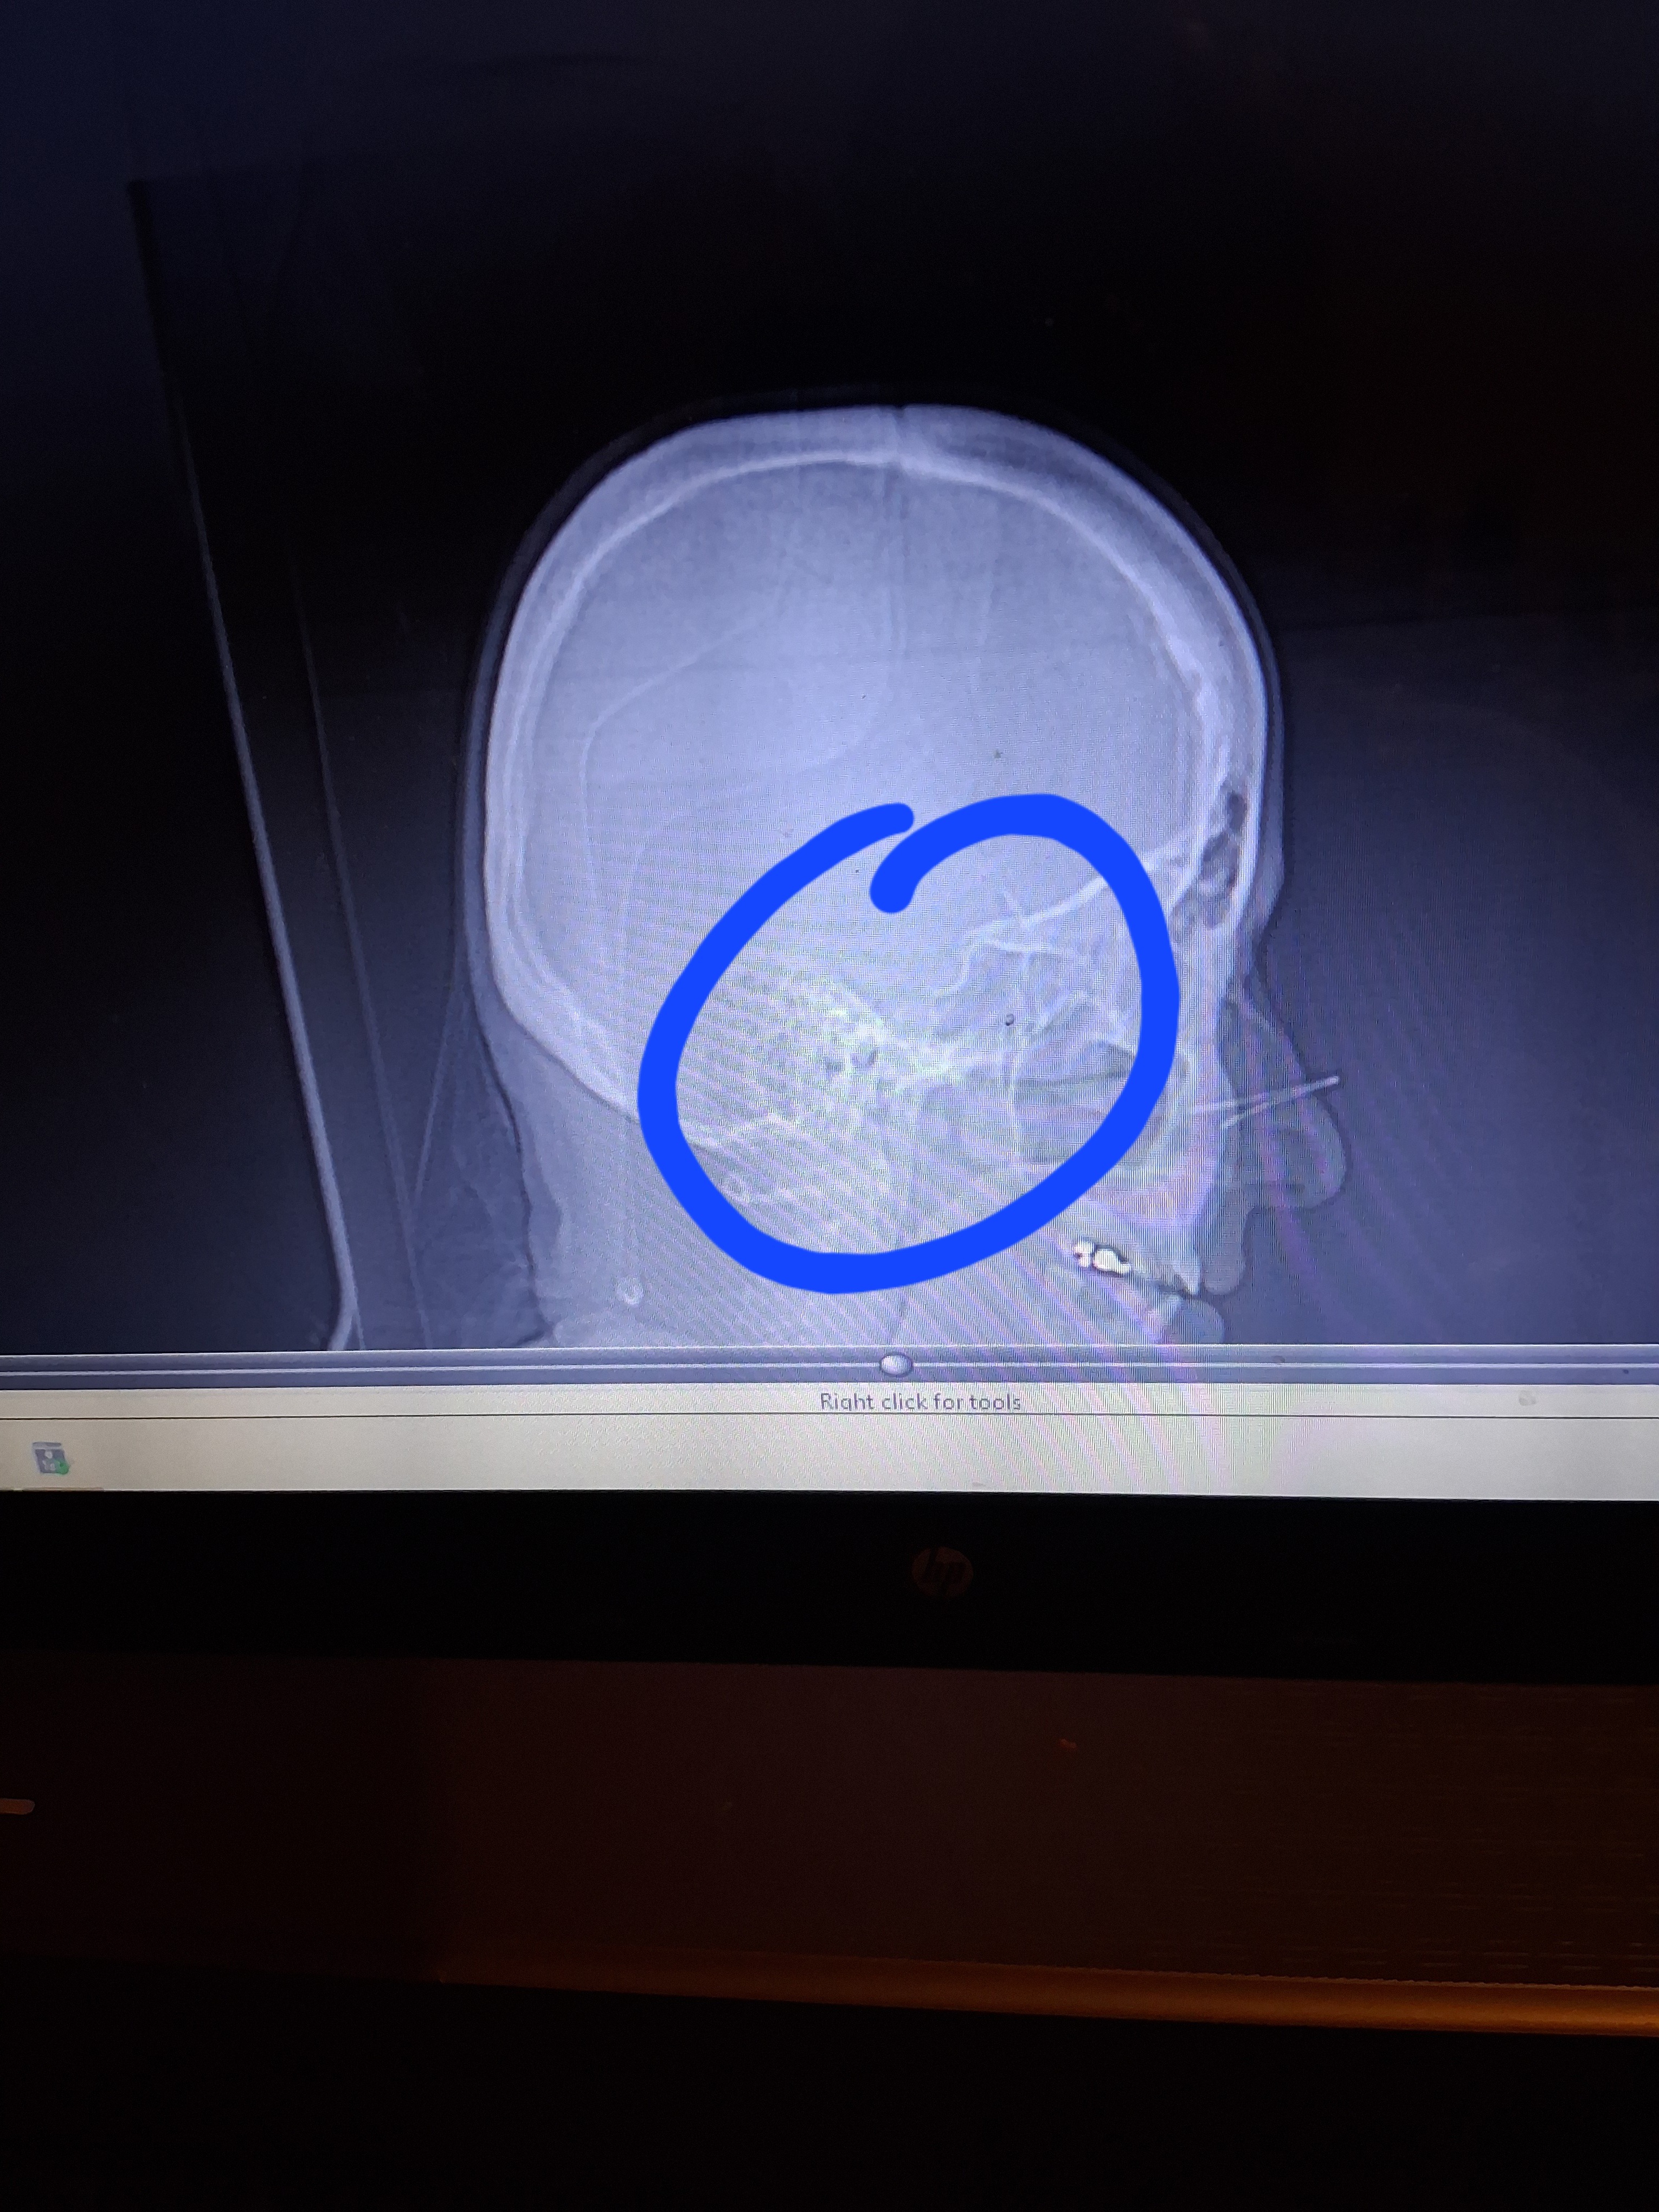

I have already 2 MRI's, and 2 C.T. scans, which showed 2 tumors, on the left side of my brain, and they are attached to one of the blood passages, on the left side of my head. I have 2 more scheduled MRI's, March 31st, and from there I will be scheduled to remove the MENINGIOMA.